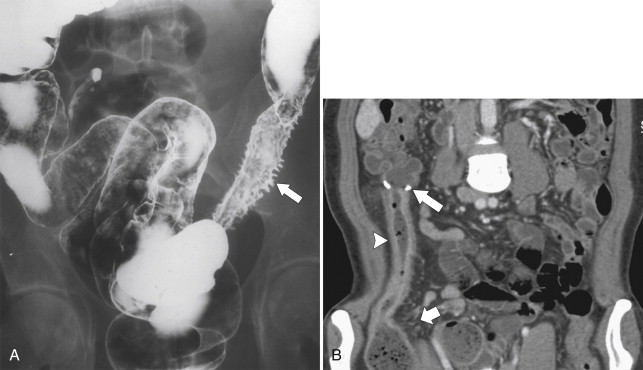

Other differentiating features of UC include a propensity for Crohn disease to fistulize with the small bowel, with adjacent organs, or to the skin. This can be assessed by CT ( Fig. 5-23 ), BE ( Figs. 5-24 and 5-25 ), or MRI ( Fig. 5-26 ). Abscess formation is also recognized in Crohn disease rather than UC ( Fig. 5-27 ). An increased risk of small and large bowel malignancies, predominantly adenocarcinomas, is associated with Crohn disease ( Fig. 5-28 ).

Figure 5-24, A and B, Axial CT and BE in a 49-year-old woman with a rectocutaneous fistula ( arrows ) due to Crohn disease.

Figure 5-25, BE in a 44-year-old woman with a coloenteric fistula ( arrows ) with a segment of jejunum ( arrowhead ) due to Crohn disease.